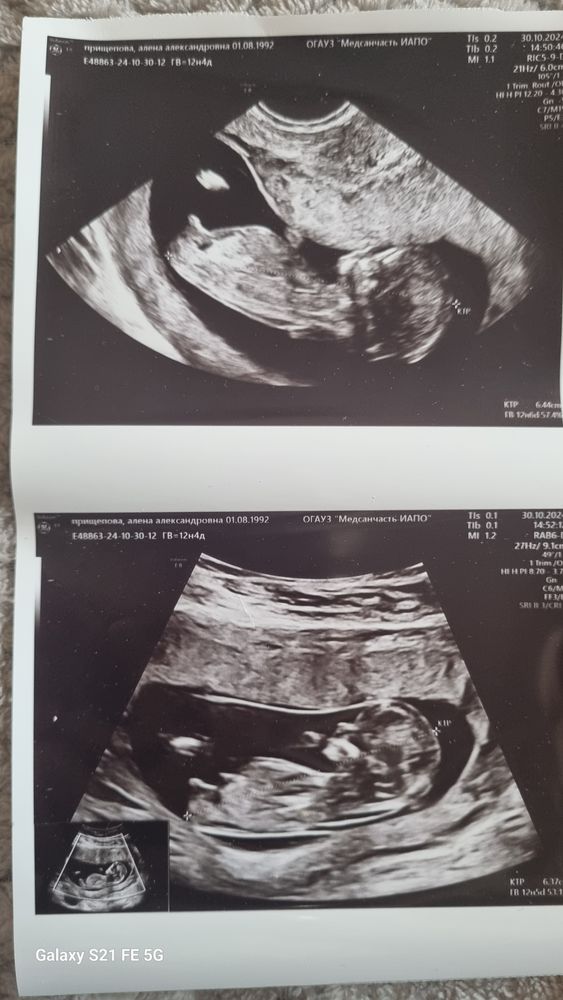

Изображение Изображение добавлю еще фото которые есть, может тут заметно 😁

25.12.2024

Изображение

Алена, мальчик в 13 недель